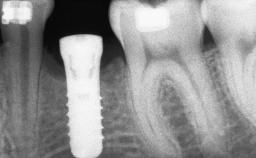

Bone Augmentation Horizontal|Sinus Floor Elevation|Staged|Vertical

Augmentation Materials Autogenous chips|Autogenous block(s)|Xenogenous|Membrane

Bone Volume Deficient vertically or deficient vertically AND horizontally